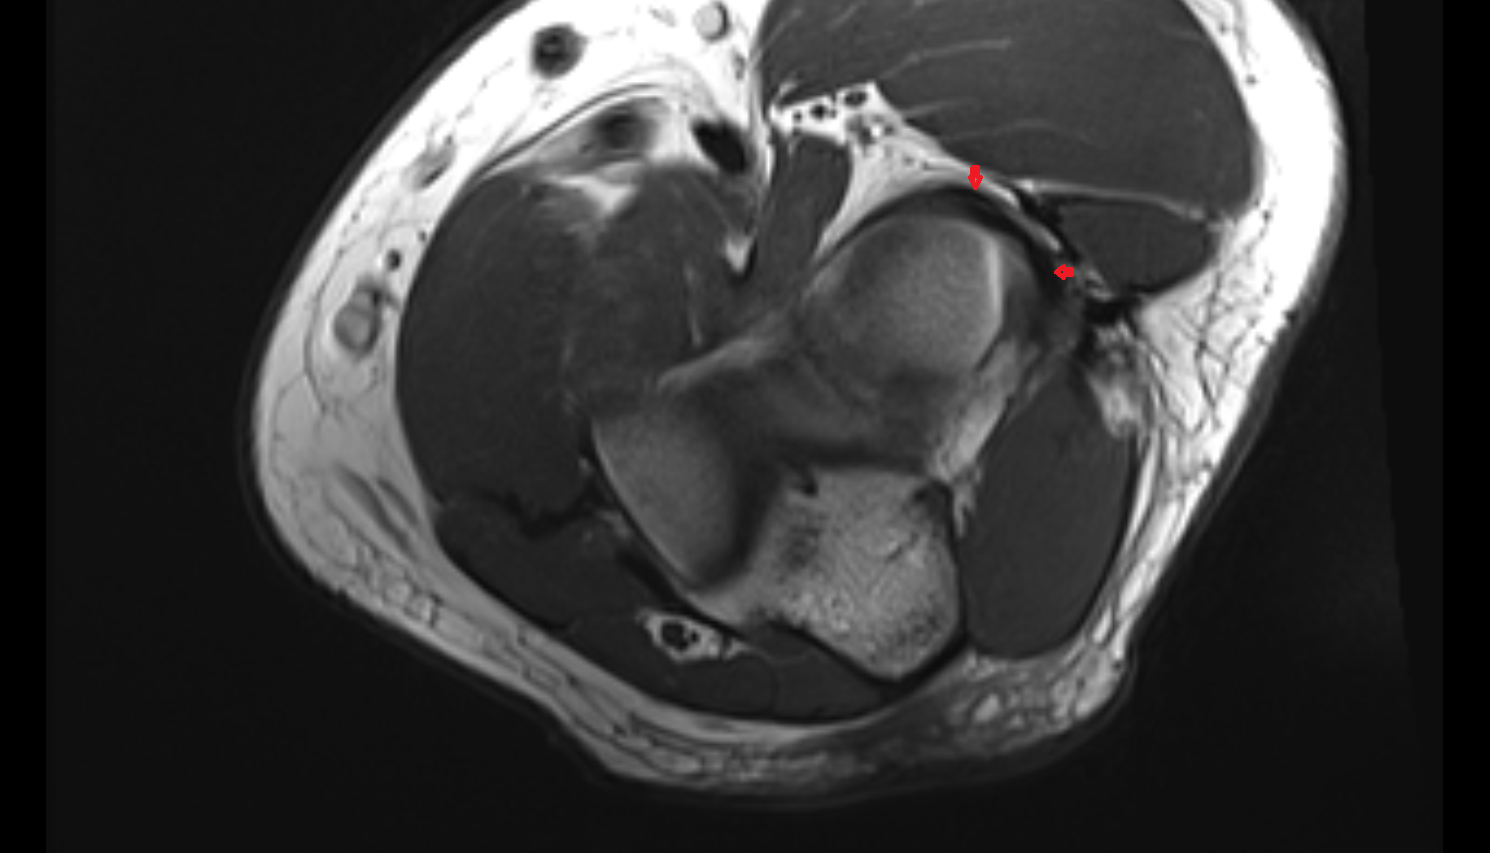

- Knee Joint